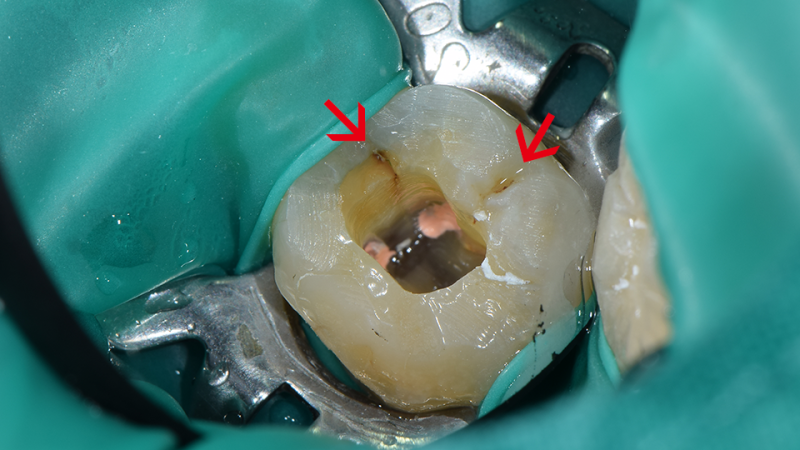

미세 현미경 치료

치과의사의 눈으로 확인할 수 없는

작은 부분까지 놓치지 않습니다

충치/치아파절 등을 정확히 진단합니다

치아를 최대 25배까지 확대하여 정밀하게 치료합니다

치료한 치아의 재발과 부작용을 최소화 합니다

정밀한 치료로 주변 조직의 손상을 최소화 합니다

일부 대학병원과 치과에서만 보유하고 있는 미세현미경은 치과의사의 눈으로 확인하기 힘든 작은 부분까지 보여주어 난이도 높은 보존치료를 효율적으로 하게 해줍니다.

미세현미경으로 보이는 것들

신경관 확보

치아 뿌리

염증 원인 발견

크랙 발견